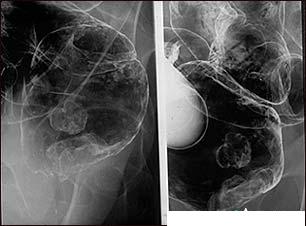

Screeningul in cancerul colorectal